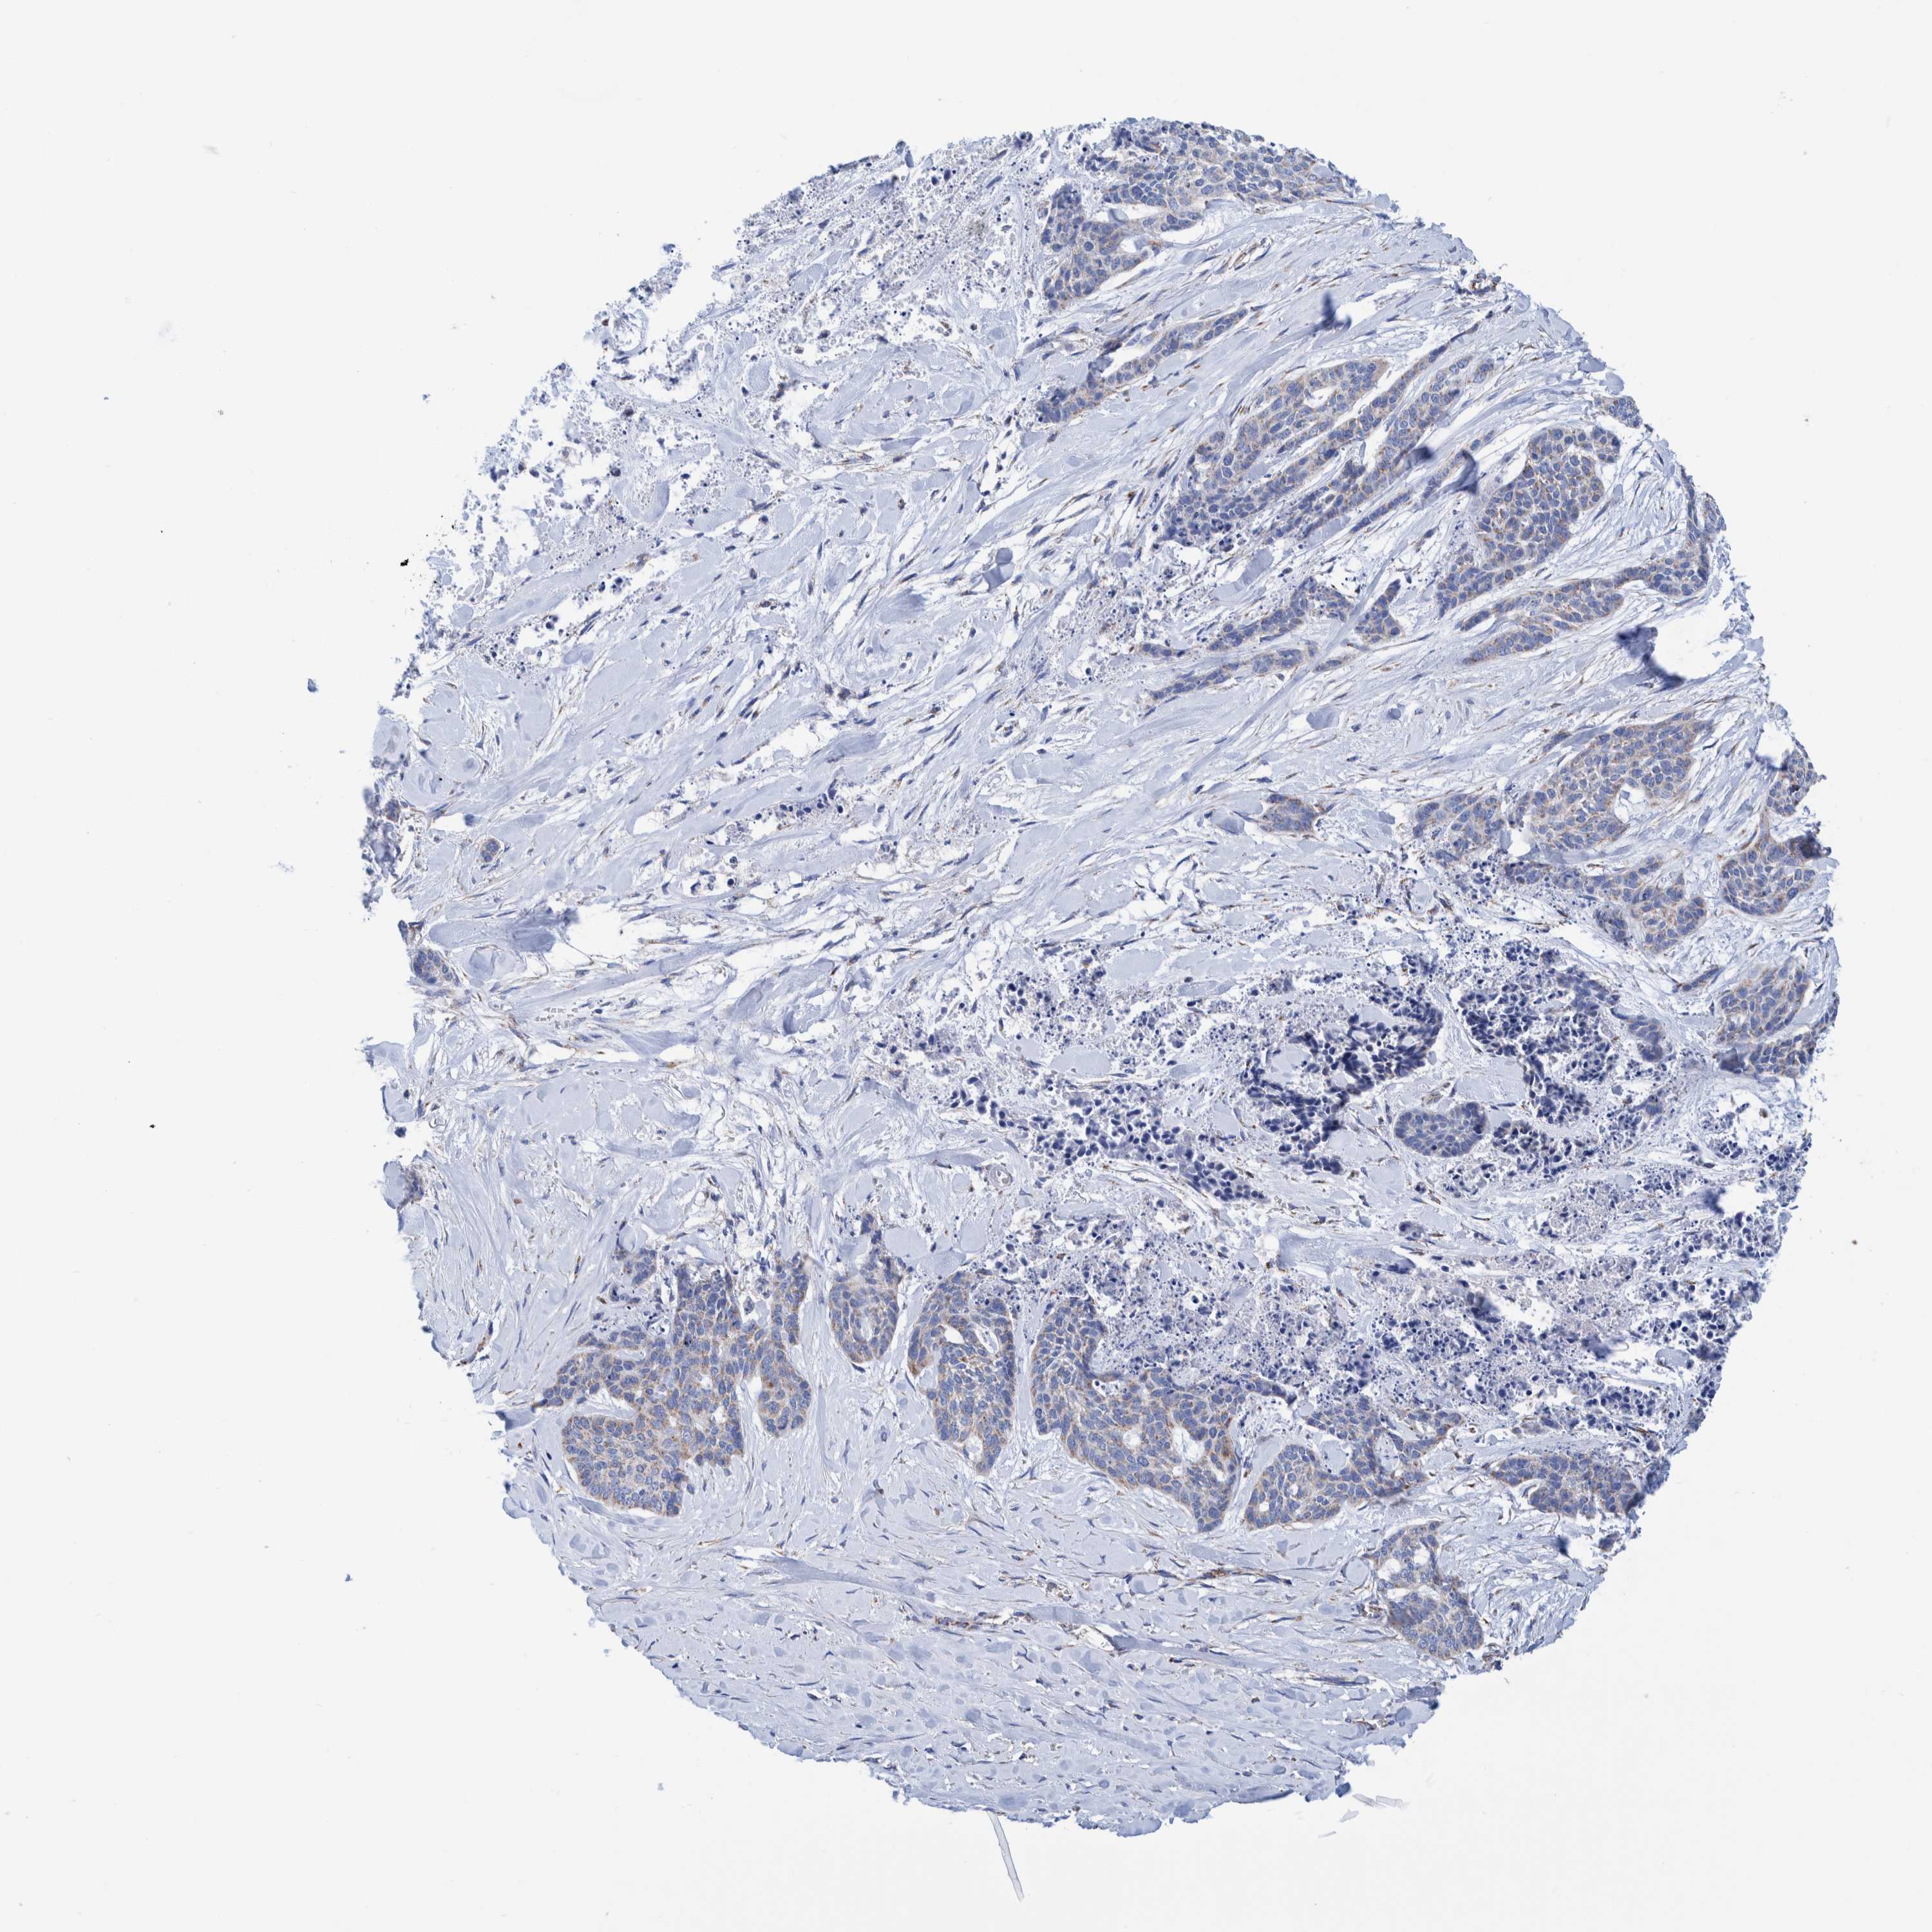

SKIN CANCER - Protein expressioni

A mouse-over function shows sample information and annotation data. Click on an image to view it in a full screen mode. Samples can be filtered based on level of antibody staining by selecting one or several of the following categories: high, medium, low and not detected. The assay and annotation is described here.

Antibody staining in the annotated cell types in the current human tissue is reported as not detected, low, medium, or high, based on conventional immunohistochemistry profiling in selected tissues. This score is based on the combination of the staining intensity and fraction of stained cells.

Each image is clickable and will lead to virtual microscopy that enables deeper exploration of all samples and also displays staining intensity scores, fraction scores and subcellular localization as well as patient and tissue information for each sample.

Antibody HPA023160

Basal cell carcinoma